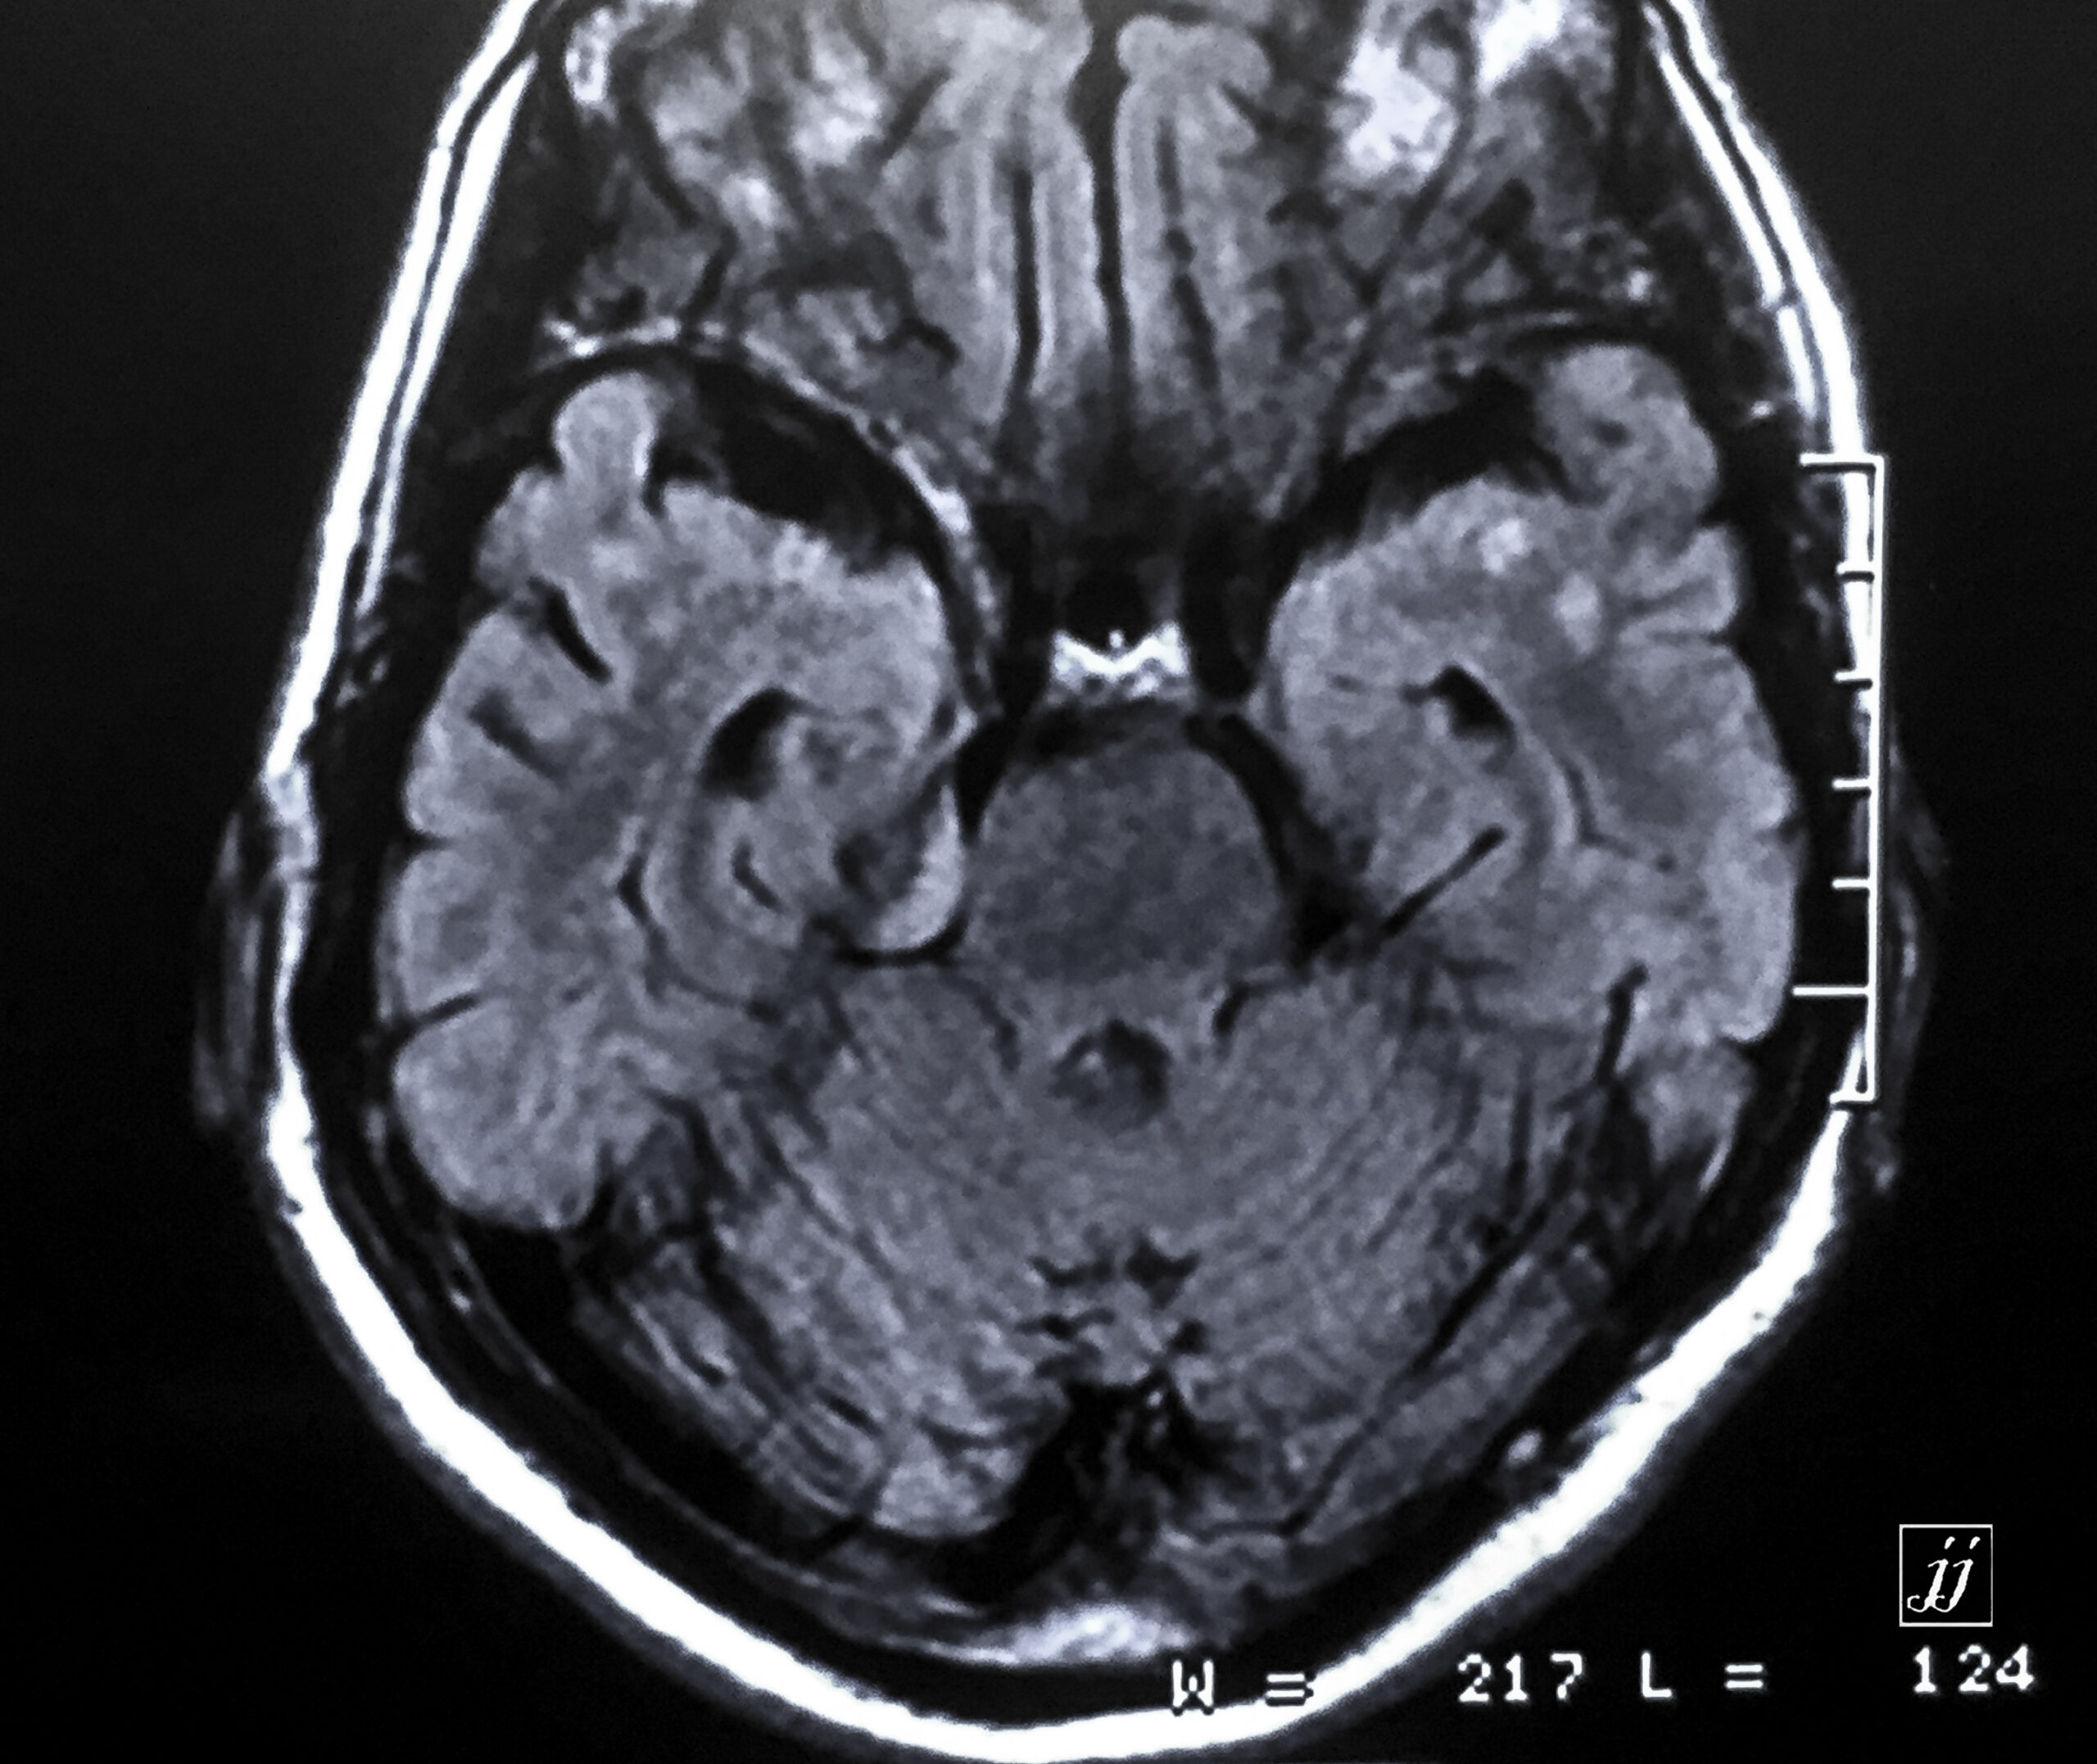

Brain- small right CPA Meningioma (4)